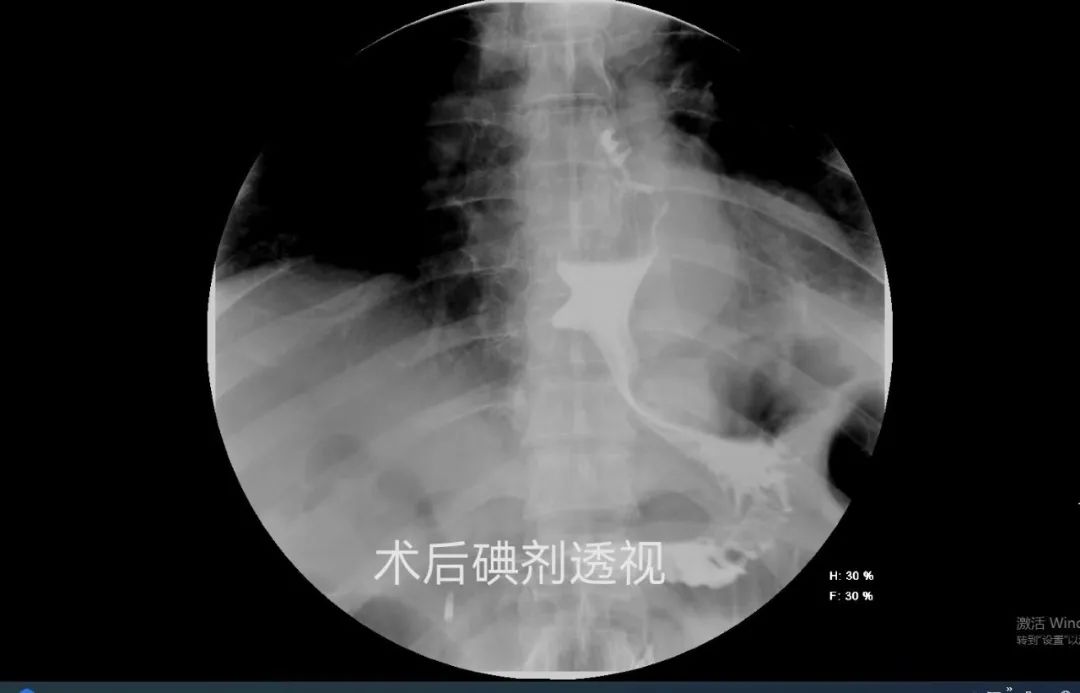

刘女士,58岁,出现进食困难近30年。她曾在多家医疗机构就诊,但病情仍反复发作并逐渐恶化,近期吞咽困难和呕吐情况加重,体重明显下降。经多方打听,她来到我院普外临床医学中心。经过详细的术前检查评估,内镜治疗组副主任孙翔宇带领团队顺利实施了经口内镜下食管括约肌切开术(POEM术)。术后恢复顺利,一周后复查碘剂食管造影显示贲门通过性良好,食管排空顺利,患者现已正常进食。